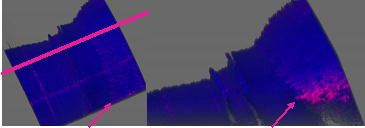

In this study, we performed OCTA scans in 10 healthy participants (6 men, 4 women, mean age 28.2 +/- 6.29 Table 2 shows demographic information of the subjects including age, sex and skin type. We scanned two subjects with deep brown skin, 3 subjects with white skin and 5 subjects ranging from light brown to moderately brown skin. Nailfold capillaries were successfully detectable in 100% of the OCTA scans. Figure 2 is an example of the OCTA scan obtained from subject 7 along with an image of the nailfold of the same digit using the traditional method for nailfold capillaroscopy. We measured the flow area and constructed a vessel density map using the built-in software of the instrument (RTVue XR, version 2016.2.0.35; Optovue Inc). Furthermore, we were able to obtain an automatic measurement of vessel density and flow area per individual scan as elucidated in Figure 3. Three-dimensional reconstructions were created and modified to allow an easy identification of the vessels and the surrounding anatomical structures. The front row of capillaries is easily identified in relation to the nail and the surface of the skin (Figure 4).

Figure 4 Three-dimensional reconstructions from Raw OCT structural and angiographic data. (Left) Coronal view depicting the first row of capillaries. (Right) sagittal view at the level of line at left image demonstrating the relationship between the front row of capillaries and the nail. Arrows point at the front row of capillaries.